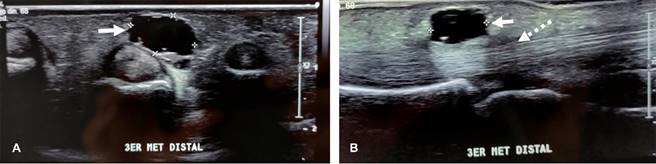

La sintomatología está determinada por su ubicación anatómica, llegando a causar compresión de estructuras adyacentes o como lesión ocupante de canales o túneles anatómicos; en la mano, se localizan principalmente en la base de los dedos o en relación a las poleas anulares de los tendones flexores (Figuras 1 y 2). Al ultrasonido, se presenta como estructura anecoica, redondeada u ovoidea de paredes ecogénicas finas bien definidas, con o sin lobulaciones o tabiques internos, que pueden ser más gruesos cuando se trata de lesiones de mayor tiempo de evolución.

Figura 1: Imágenes de ultrasonido diagnóstico de palma de mano derecha. A) Corte transversal, mostrando: imagen anecoica redonda de 1.5 cm de diámetro, con pared fina ecogénica, correspondiendo a quiste sinovial de la vaina del tercer dedo de mano derecha (flecha). B) Corte transversal mostrando el quiste mencionado y la estructura fibrilar indemne del tendón flexor (flecha punteada) del tercer dedo.